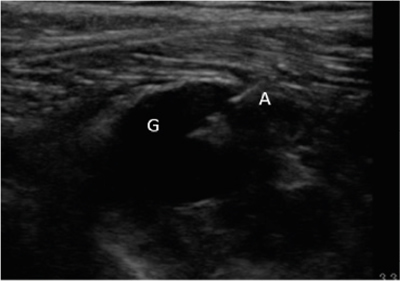

Neuropatía peronea secundaria a ganglión extraneural: revisión de literatura y propuesta de tratamiento. Caso no positivo

Peroneal neuropathy caused by an extraneural ganglion: literary review and treatment proposal. A non-positive case

Este artículo presenta el caso de un paciente de 69 años con una neuropatía compresiva peronea secundaria a un ganglión, inicialmente interpretada como una radiculopatía L5. Este incorrecto enfoque supuso la sobremedicación del paciente, un mal control algésico, la realización de una discectomía L4-L5 innecesaria y una pobre evolución neurológica.

Figura 1